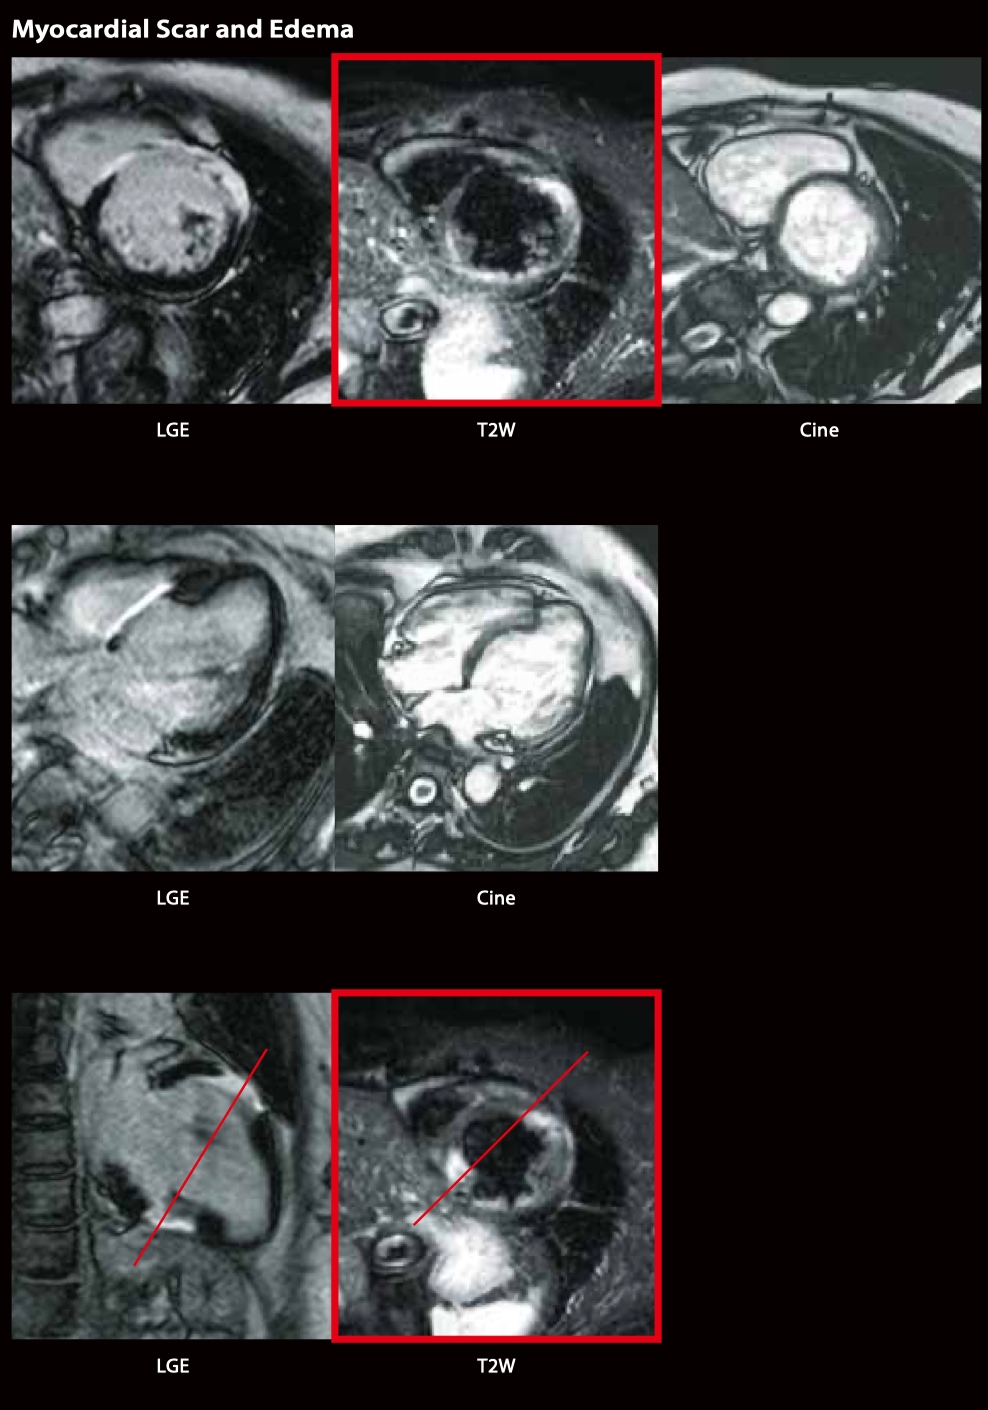

Кіно МРТ показала асиметричну гіпертрофію перетинки, що характерно для ГКМП. Систолічна функція ЛШ збережена.

Гіпертрофована перегородка має високу інтенсивність сигналу на пізньому посиленню гадолінію, що свідчить про фіброз. На T2W чорної крові гіпертрофована перегородка мала високу та низьку інтенсивність сигналу, що вказує на змішаний стан набряку міокарда та фіброзу.